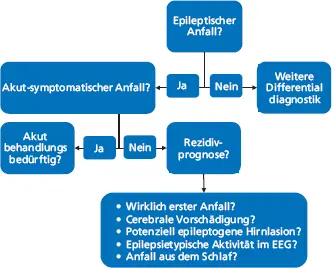

Nach einem ersten Anfall sind nach Bast et al. (2017) die in Abbildung 1.2 dargestellten Fragen zu beantworten. Die in Tabelle 1.1 genannten Untersuchungen beantworten diese.

Abb. 1.2: Fragen, die nach einem erstmaligen Anfall zu beantworten sind (Specht und Bien 2018, © Georg Thieme Verlag KG)